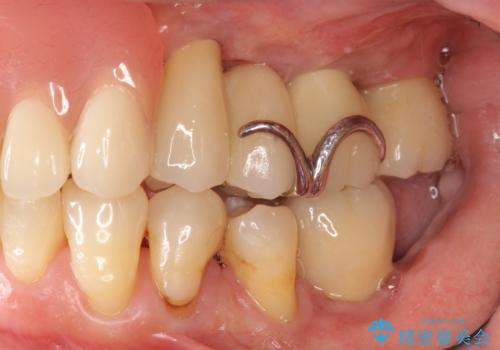

- 歯が全体的にグラグラし、しっかりと物が噛めなくなり歯周病治療を希望され来院されました。

残すことのできる歯、残すことのできない歯を初期治療を進めながら見極め、最終的に臼歯部はインプラント、上顎前歯は入れ歯による補綴計画となりました。